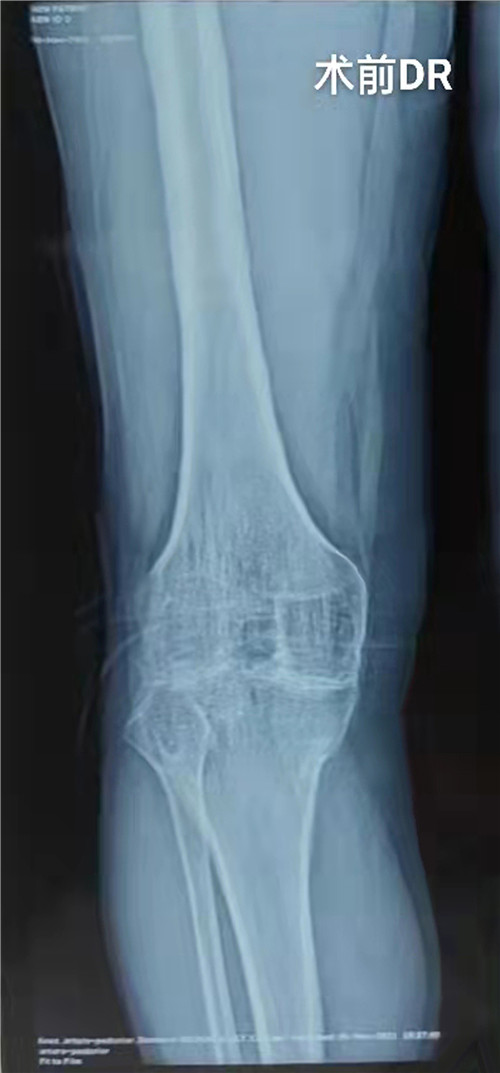

患者约15年前右膝关节受伤后致髌骨骨折,因当地医疗条件受限予以保守治疗后畸形愈合,膝关节畸形、功能障碍,后曾在外地就诊,实行了2次右膝关节软组织松解术,无明显改善。15年来症状逐步加重,现右膝关节呈屈膝15°强直畸形,饱受痛苦,患者为改善生活质量来市三院就诊,入院后经查体及完善相关检查,明确诊断为:右膝创伤性关节炎右膝关节融合;右髌股关节融合。